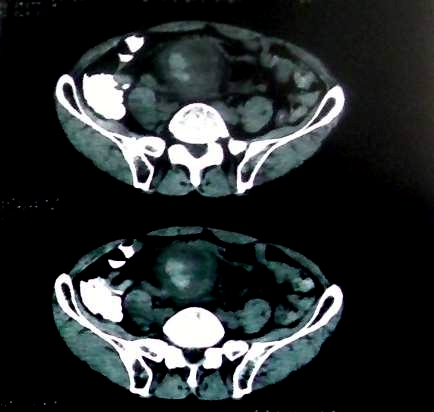

男 60岁,下腹部肿块半年余

前列腺肥大,密度不均。伴盆腔实性肿块。考虑前列腺癌伴盆腔转移。建议增强扫描。

考虑来源于肠道的肿瘤,乙状结肠?询问排便情况

盆腔恶性占位,间质瘤可能性大

乙状结肠间质瘤

盆腔恶性占位,间质瘤可能性大。

考虑盆腔内间质瘤可能性大。

病理结果:肠系膜肉瘤

肠系膜的原发性肠系膜肿瘤比较少见,大体可分为囊性和实性两类。囊性肿瘤多为良性。实性肿瘤可以为良性和恶性,恶性肿瘤以恶性淋巴瘤为最多,其次是脂肪肉瘤、平滑肌肉瘤、纤维肉瘤等。恶性肿瘤约占实体肿瘤的6% [1] 。文献资料显示原发性肠系膜肿瘤约7%位于小肠系膜,其中60%位于回肠系膜和肠系膜根部,结肠系膜和阑尾系膜仅占20%左右 [2] 。由于肠系膜肿瘤在临床上不多见,症状无特异性,起病隐匿,早期可无症状,只有当肿瘤增大压迫周围的组织脏器时,才有可能出现相应的症状,并且这些症状常与邻近器官受压有关。腹部包块是主要的症状,临床表现为发热、乏力、腹部隐痛不适和饱胀感、消瘦,偶有呕吐及便秘,当肿瘤出血和囊肿突然增大时,可有腹痛,压迫症状有肠梗阻,下肢肿胀,肾盂积水等表现。体格检查时可触及腹部肿块,且活动度好,尤其是横向移动。b超可早期发现腹块,并可确定大小、性质及部位。x线钡剂灌肠检查,虽然不能提供系膜肿瘤的直接诊断依据,可显示为与肠管关系密切之外在性肿物,并可排除肠管、泌尿系等疾病[3] 。腹腔镜对原因不明的腹痛及性质不明的腹块,既可定性又可定位,其正确诊断率为74% [4] 。肠系膜良性肿瘤和恶性肿瘤的病程长短进行比较,恶性肿瘤绝大多数病程均在半年以内,没有超过2年以上。良性肿瘤大多数病程均在2年以上。这一点在诊断上具有鉴别意义。

病灶形态不规则,偏心性裂隙样坏死,支持恶性病变。来源不好定。感谢反馈结果--肠系膜肉瘤。